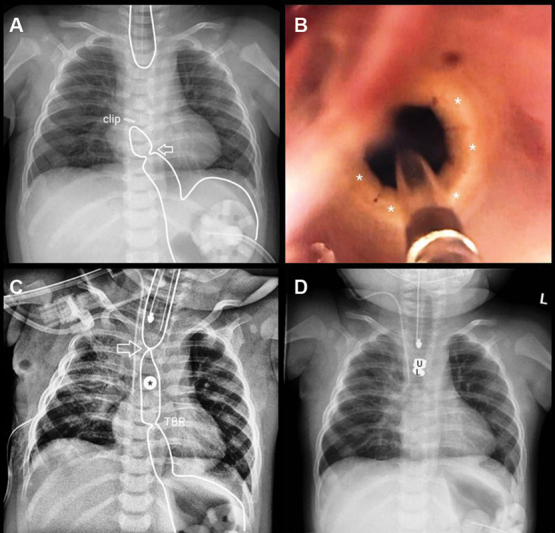

Esophageal atresia (EA) repair can be complicated by associated malformations such as a tracheobronchial remnant in the distal esophagus. We describe our experience with a patient found to have long-gap EA with a distal cartilaginous ring who was managed using a combination of esophageal lengthening and magnetic compression anastomosis. A 5-month-old girl was referred to us from an outside hospital with type C EA including a very high upper pouch. She had undergone a prior thoracotomy with fistula ligation during which a clip was placed on the lower esophagus, leaving a 2-cm diverticulum on the trachea and a short lower esophageal pouch. Upon endoscopic evaluation at our center, we found a tracheobronchial remnant in the lower esophagus between the clip and the carina. An open thoracotomy was performed to approximate the esophageal pouches and a magnet anchor (Connect EA, Myka Laboratories, San Francisco, California, United States) was placed retrograde through the distal esophageal cartilaginous ring into the lower pouch. On postoperative day 8, after adequate growth and decreased pouch tension, a second magnetic anchor was placed endoscopically to the upper pouch to mate with the previously placed lower pouch anchor. The anastomosis formed within 14 days. Due to the tracheobronchial remnant, the device did not pass distally and was removed endoscopically. On postoperative day 8, balloon dilation of the anastomosis and tracheobronchial remnant was performed. Subsequently, the patient required a total of 6 dilations in an 18-month follow-up. This case report illustrates the utility of using magnets to create an esophageal anastomosis in complex cases of EA with concomitant esophageal malformations. The parents of the patient gave their written consent to publish this technical report.